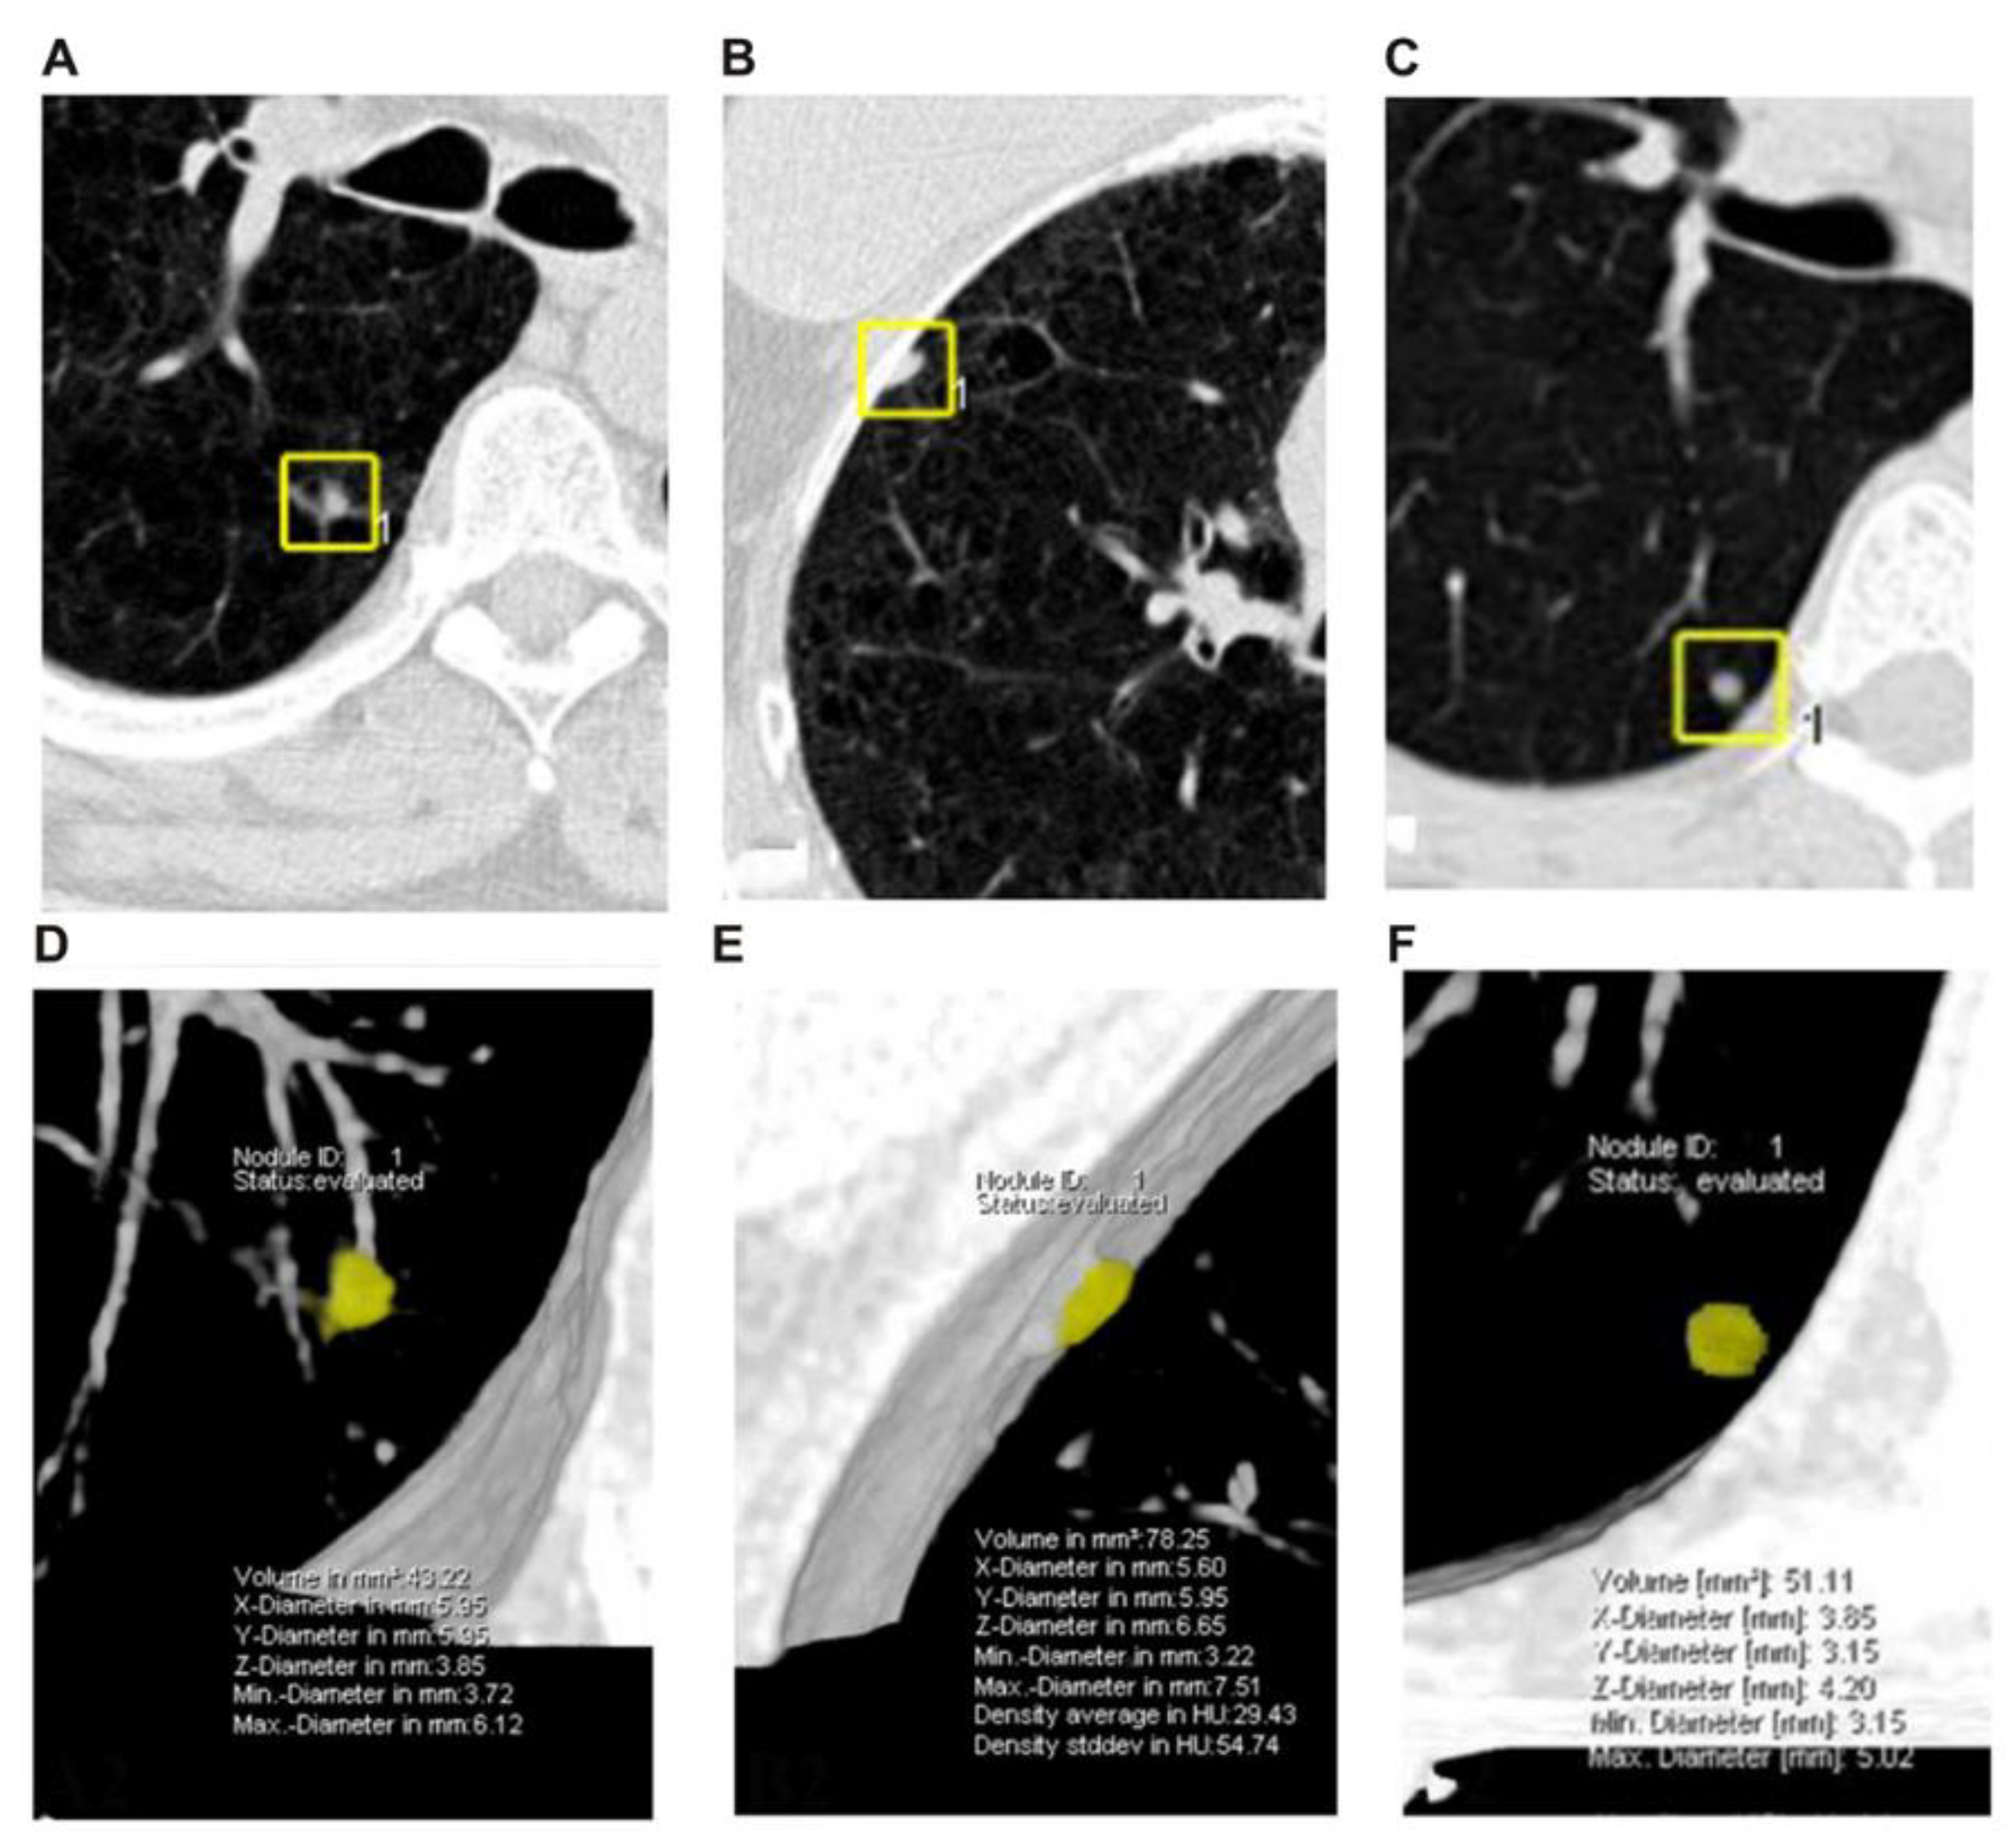

2.3. Linear and Volumetric Measurements of the Nodule

2.4. Definitions of Nodules